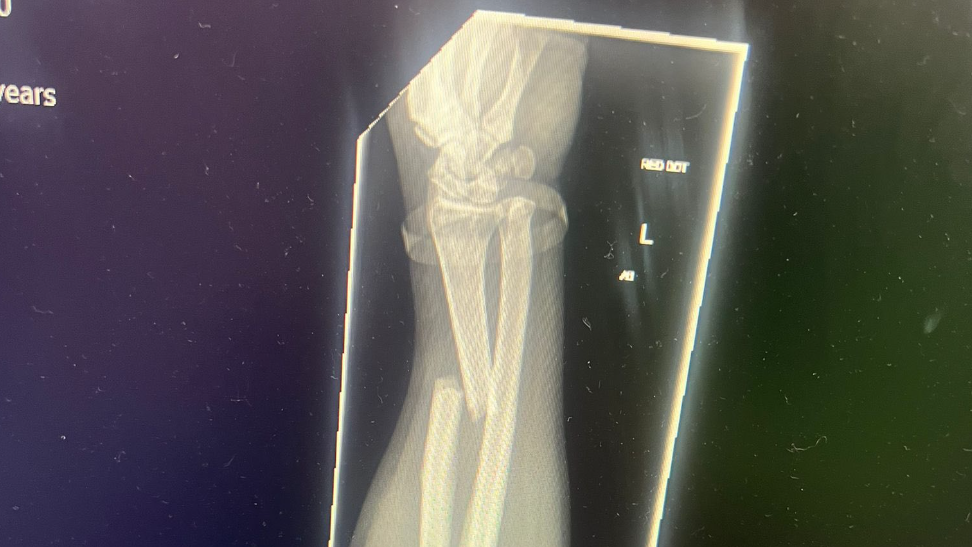

Jamie Coward “nervous and worried” before racing return after North West 200 crash

Following injuries picked up at the North West 200, Jamie Coward has made his return to racing.